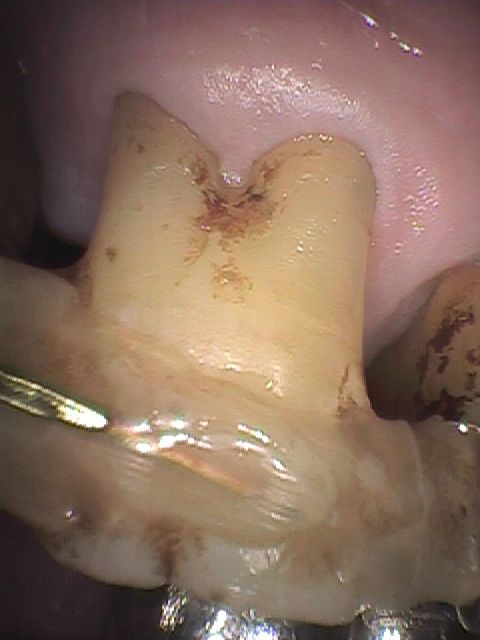

仮固定はタイムリーに実施しますと非常に有効な処置にもかかわらず、ここ十数年の間で重症になられてFDCに転医されている患者さんには、なぜかこの処置をおこなった形跡が見あたらないようです。以下に示します症例はCT読影の結果、歯槽骨の吸収が著しく、そのため強度の歯の動揺、さらに出血も相当ありました。

仮固定の効果

しかし、仮固定と共に歯周ポケットの「病原菌除菌」とレーザー治療などによる歯周組織の「ダメージ回復」を統合的に実施しますと短期間で病状が改善し咀嚼も普通にできるようになっています。(Photo.4-1, Photo.4-2)